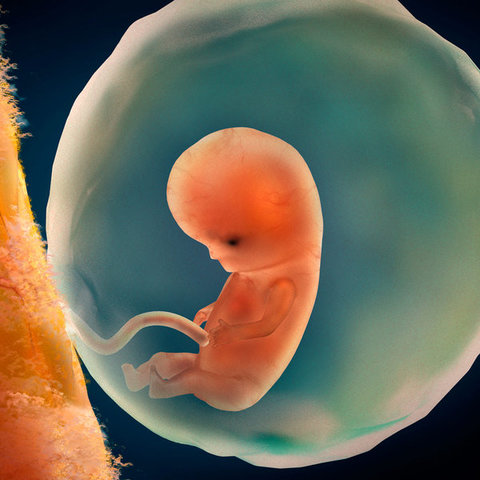

Semana 6

En esta semana es cuando el corazón comienza con

latidos regulares que por lo regular no se detectan

aun en la ecografía, también comienza a tener

ligeros movimientos que aún no se perciben pues su

tamaño es de aproximadamente 1 centímetro de

largo.Progresa el desarrollo de la traquea, la laringe

y bronquios. Lacavidad oral y nasal comienzan a

separarse, se forma el paladar. Se desarrollan más la

piernas y los brazos que parecen aletas.